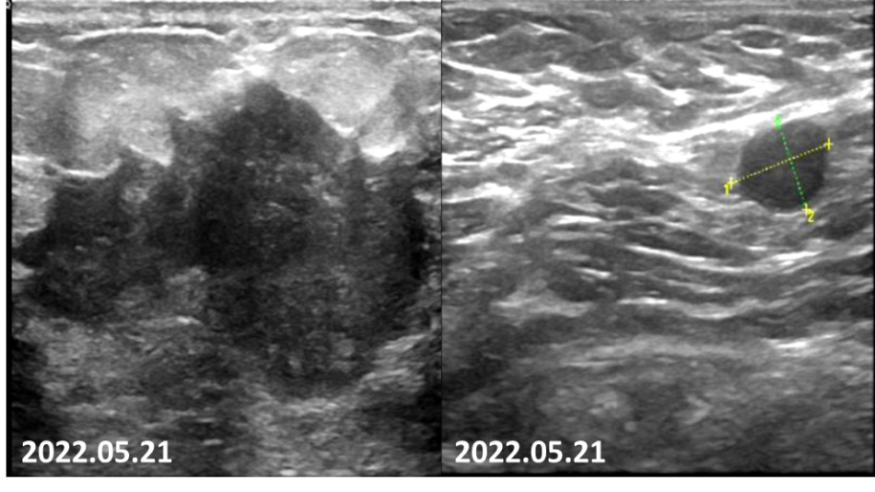

2022-05-21乳腺超声报告:左乳可见多处低回声结节,较大者位于12点钟,大小约47mm×27mm×35mm,距体表10mm,距乳头35mm,形态不规则,边缘成角,内回声不均匀。CDFI:内可及点状血流信号。左侧腋窝可见数个淋巴结回声,髓质消失,较大者大小约12mm×8mm,CDFI:内可见点状血流信号。右侧腋窝及双侧锁骨上窝未见明显肿大淋巴结。

图2.患者乳腺彩超可见肿瘤毛刺征明显,呈浸润性生长,腋窝淋巴结形态失常。

2022-07-08乳腺超声:左乳可见多处低回声结节,较大者位于12~1点钟,大小约20.6mm×6mm×18.3mm,距体表12mm,距乳头26mm,形态不规则,边缘成角,内回声不均匀,CDFI:内可及点状血流信号。左侧腋窝可见数个淋巴结回声,髓质消失,较大者大小约18mm×8mm,CDFI:内可见点状血流信号。右侧腋窝及双侧锁骨上窝未见明显肿大淋巴结。

图5.2疗程后可见患者左侧乳房肿物仅余核心部分,左腋窝淋巴结形态已接近正常。